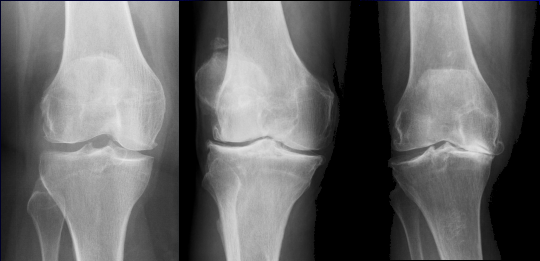

Arthrose ist eine degenerative Gelenkerkrankung, die durch den Abbau von Knorpelgewebe in den Gelenken gekennzeichnet ist. Diese Erkrankung betrifft vor allem ältere Menschen, kann aber auch bei jüngeren Personen auftreten. Die häufigsten Ursachen für Arthrose sind übermäßige Belastung der Gelenke, genetische Veranlagung, Verletzungen oder Entzündungen.

Die Symptome von Arthrose umfassen Schmerzen, Steifheit, Schwellungen und eingeschränkte Beweglichkeit der betroffenen Gelenke. Diese Beschwerden können im Verlauf der Erkrankung zunehmen und die Lebensqualität der Betroffenen erheblich beeinträchtigen.